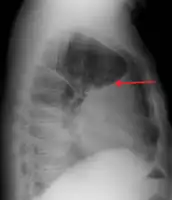

A large left sided pleural effusion as seen on an upright chest X-ray

Imaging

A pleural effusion appears as an area of whiteness on a standard posteroanterior chest X-ray.[9] Normally, the space between the visceral pleura and the parietal pleura cannot be seen. A pleural effusion infiltrates the space between these layers. Because the pleural effusion has a density similar to water, it can be seen on radiographs. Since the effusion has greater density than the rest of the lung, it gravitates towards the lower portions of the pleural cavity. The pleural effusion behaves according to basic fluid dynamics, conforming to the shape of pleural space, which is determined by the lung and chest wall. If the pleural space contains both air and fluid, then an air-fluid level that is horizontal will be present, instead of conforming to the lung space.[10] Chest radiographs in the lateral decubitus position (with the patient lying on the side of the pleural effusion) are more sensitive and can detect as little as 50 mL of fluid. At least 300 mL of fluid must be present before upright chest X-rays can detect a pleural effusion (e.g., blunted costophrenic angles).